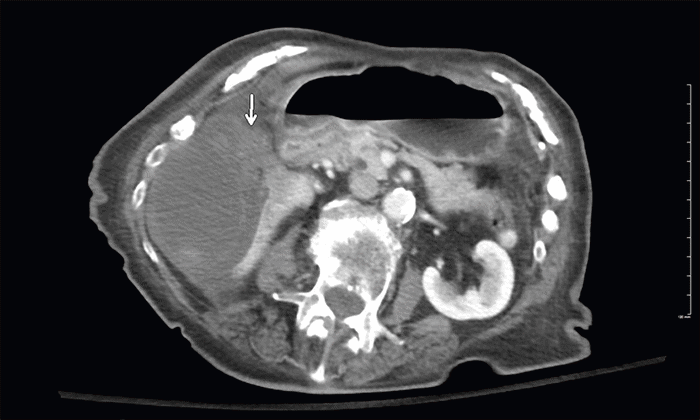

Due to the nonspecific nature of her pain, she underwent an abdominopelvic computed tomography (CT) examination. Her examination demonstrated a markedly distended gallbladder with profuse pericholecystic edema and mild gallbladder wall thickening (Figure 1). Dependent gallstones were noted in the fundus, but no obstructing radiopaque gallstone was identified. Additional findings of an eccentrically positioned gallbladder were noted, with soft tissue thickening at the gallbladder neck and heterogeneously hyperattenuating material in the perihepatic space. The concern for gallbladder volvulus was raised with likely a contained perforation containing probable hemorrhagic debris. In the setting of the unusual soft tissue thickening at the neck, an underlying obstructing neoplasm was also suggested as a differential consideration.

Figure 1. Axial Abdominopelvic CT. Published with Permission

Image demonstrates a significantly distended gallbladder with a contained pericholecystic fluid collection secondary to perforation. Thickened soft tissue density at the pedicle suggested gallbladder volvulus (arrow). Note significant mass effect on the inferior right hepatic lobe.